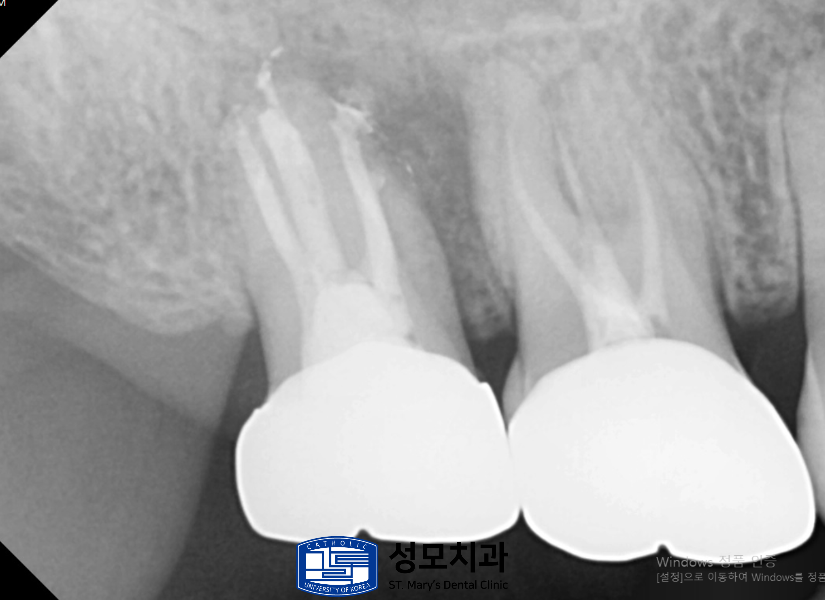

3. 크라운 제거 후

기존의 크라운을 제거해서 보니

치아 내부가 아말감으로 가득 차 있는 상태였습니다.

아말감은 금속성 수복 재료로 단단하기 때문에

견고성에는 도움이 되지만

시간이 지날수록 수축하는 성질이 있기 때문에

내부 균열이 발생해서 2차적인 문제가 발생할 수 있습니다.

그래서 크라운 내부의 아말감을

모두 제거한 뒤 재신경치료를 시작하였습니다.

4. 재신경치료 후 소독 및 밀봉

정밀한 근관치료 후 치아 내부는

다시 철저히 소독 및 밀봉하였습니다.